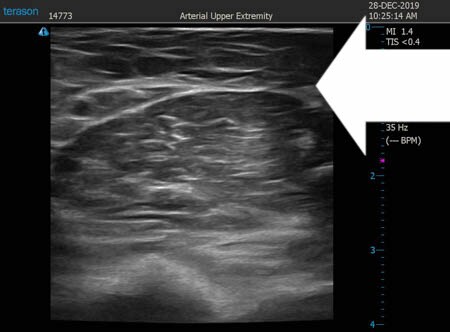

いつものように3Dタッチビュー(超音波)で

皮下脂肪層を評価してみましょう。

右二の腕

↓ ↓ ↓

上の画像の部分の皮下脂肪層をつまんでみましょう。